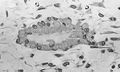

Osteoblasts (blue) rimming a bony spicule (pink - on diagonal of image). In this routinely fixed and decalcified (bone mineral removed) tissue, the osteoblasts have retracted and are separated from each other and from their underlying matrix. In living bone, the cells are linked by tight junctions and gap junctions, and integrated with underlying osteocytes and matrix H&E stain. | |

Hematoxylin and eosin staining (H&E) shows that the cytoplasm of active osteoblasts is slightly basophilic due to the substantial presence of rough endoplasmic reticulum. The active osteoblast produces substantial collagen type I. About 10% of the bone matrix is collagen with the balance mineral.[2] The osteoblast's nucleus is spherical and large. An active osteoblast is characterized morphologically by a prominent Golgi apparatus that appears histologically as a clear zone adjacent to the nucleus. The products of the cell are mostly for transport into the osteoid, the non-mineralized matrix. Active osteoblasts can be labeled by antibodies to Type-I collagen, or using naphthol phosphate and the diazonium dye fast blue to demonstrate alkaline phosphatase enzyme activity directly.

Light micrograph of decalcified (a process that removes the mineral) cancellous bone displaying osteoblasts actively synthesizing osteoid, containing two osteocytes.